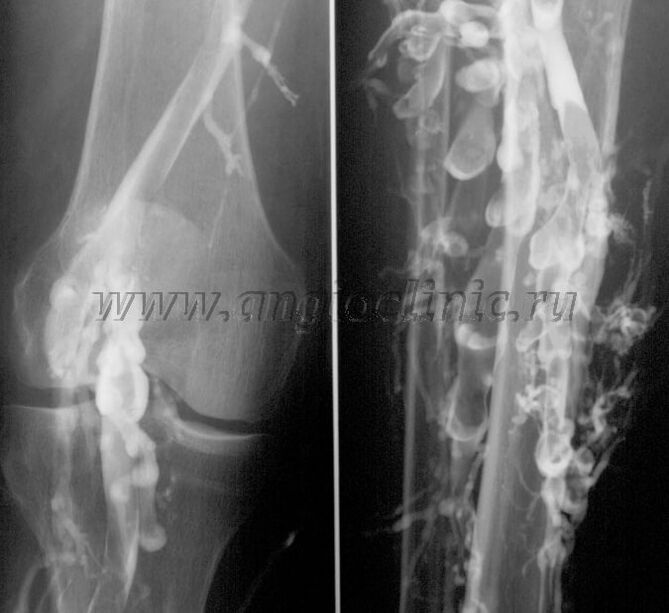

Venografia con contrasto

Di solito, l'ecografia è sufficiente per una diagnosi completa della patologia venosa, ma in alcuni casi è necessario studiare la relazione tra lo stato del sistema venoso profondo e superficiale, soprattutto in caso di recidive di vene varicose e vene varicose secondarie.

Per risolvere questi problemi viene utilizzato l'esame radiografico con contrasto. Le vene safene vengono perforate e viene somministrato il contrasto. Il movimento del contrasto viene osservato sul monitor della macchina a raggi X e vengono eseguiti tutti i test e le proiezioni necessarie. Attualmente, la venografia per le vene varicose viene utilizzata molto raramente.